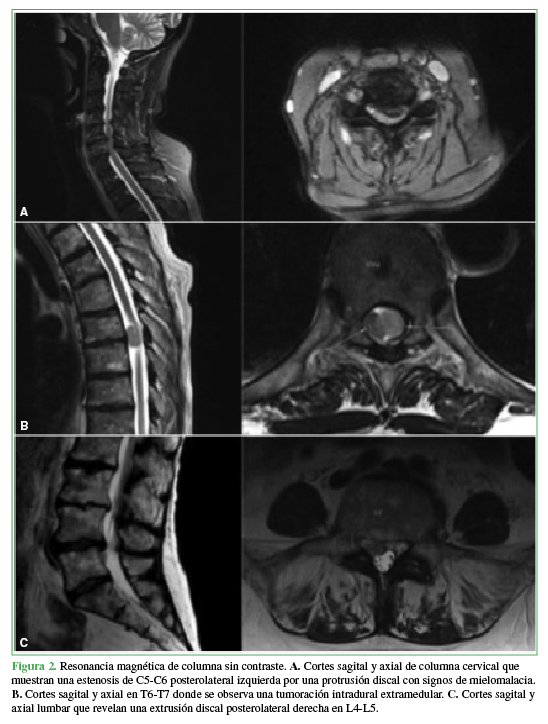

En una resonancia magnética de urgencia, se detectaron tres puntos de estenosis del canal raquimedular: 1) un canal estrecho cervical degenerativo en C5-C6 con mielomalacia focal; 2) una tumoración intrarraquídea intradural extramedular en T6-T7 con impronta en la médula espinal, de 15 mm x 8 mm x 7 mm; y 3) una extrusión discal posterolateral derecha de L4-L5 (Figura 2).